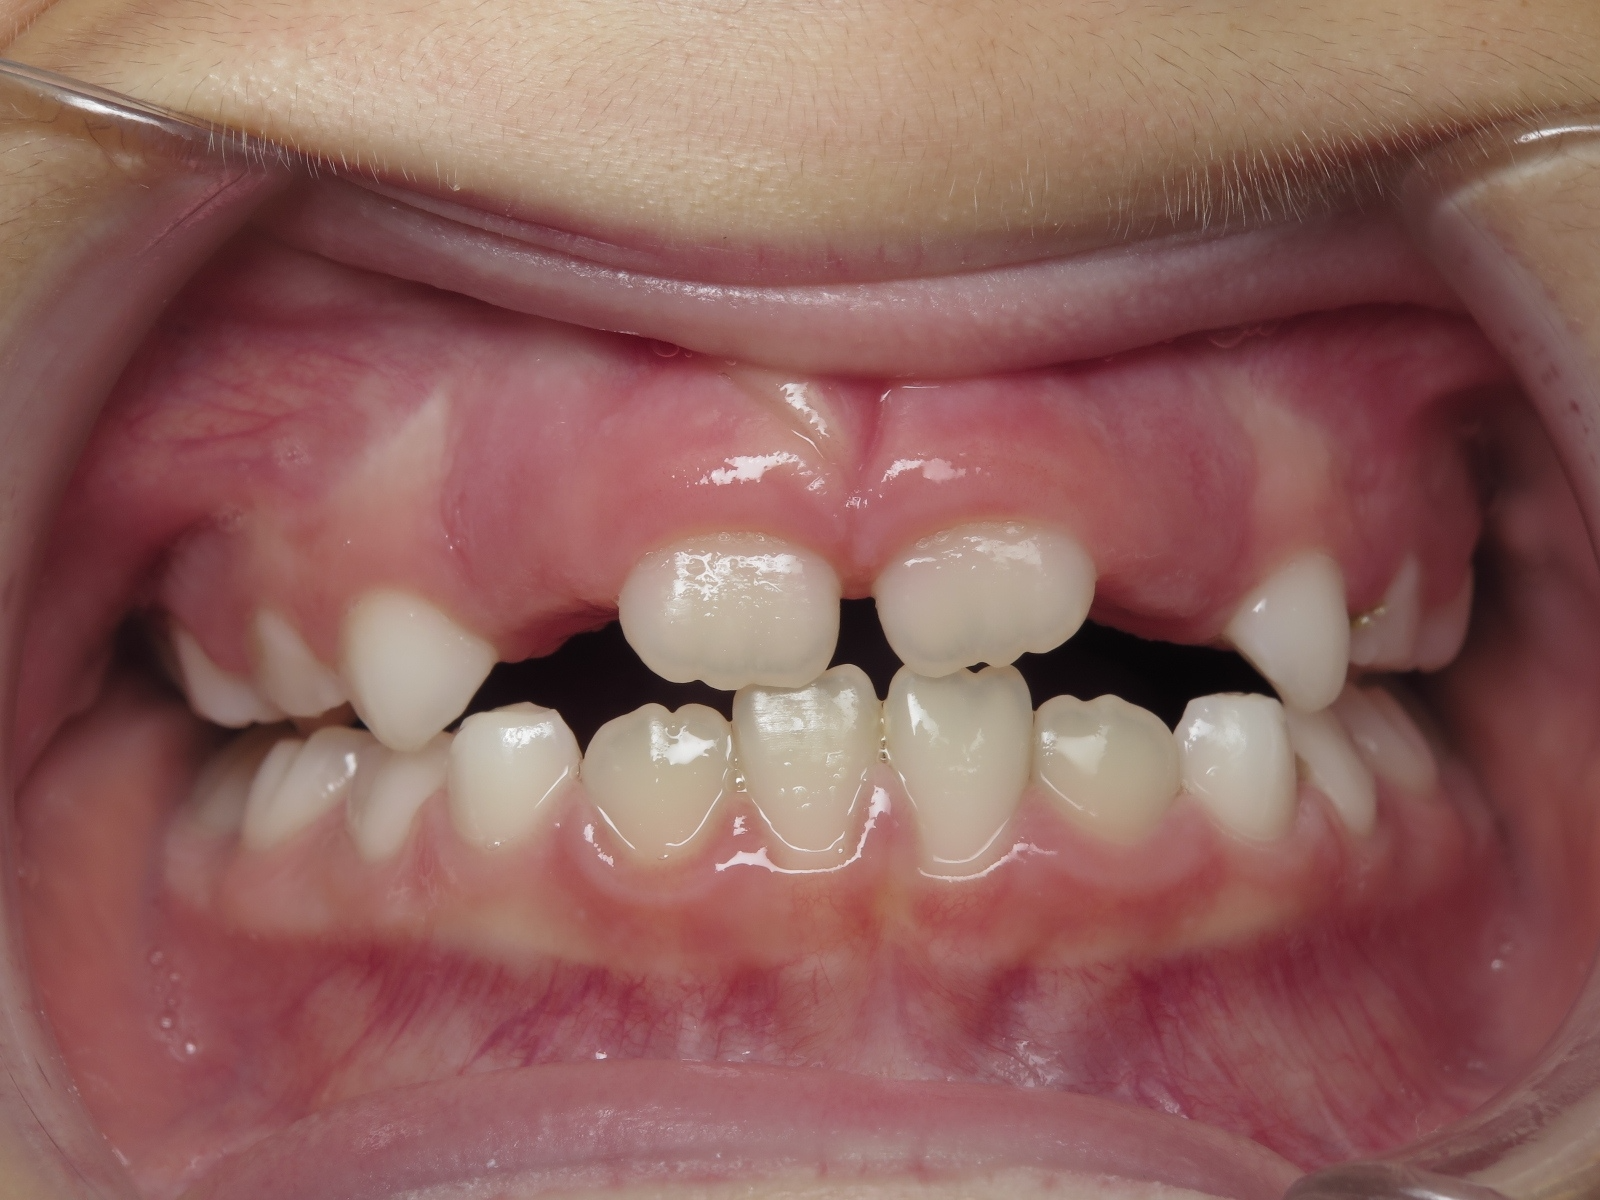

25. bout à bout anterieur 6 ans

dents du haut bout à bout par rapport à celle du bas